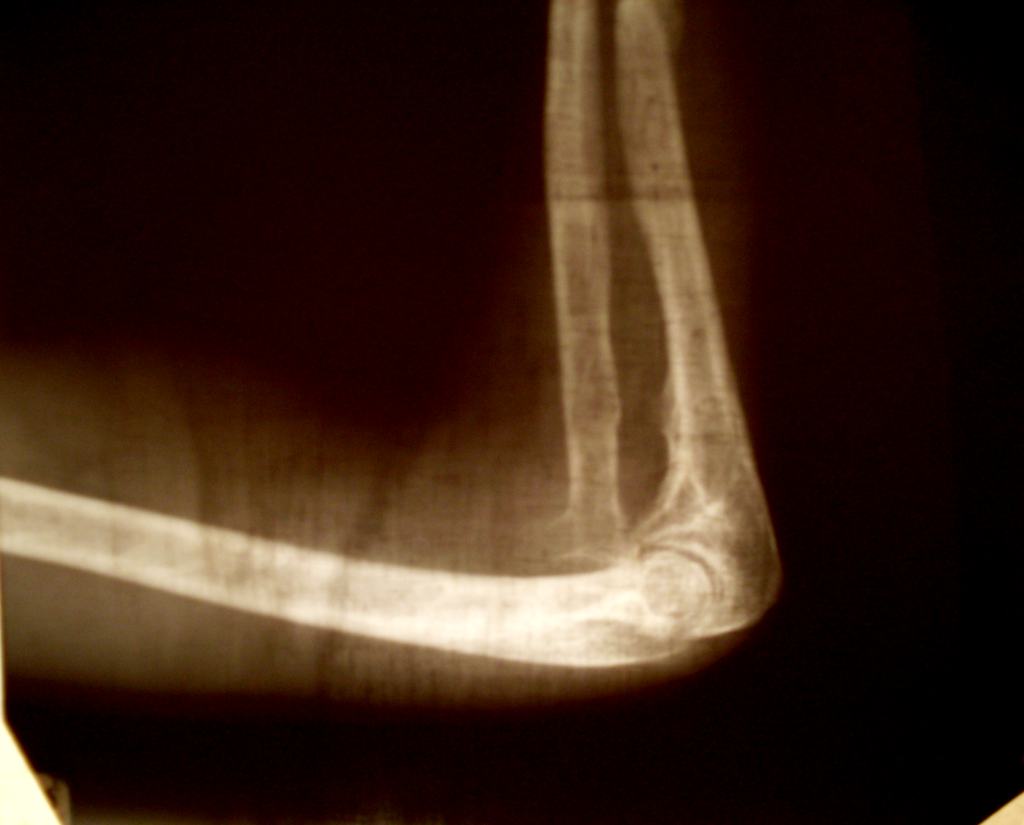

А без эндопротезирования в вашей клинике не наращивают суставы искуственно или еще как нибудь, потому что сустав хоть и болит безперестанно но он функциотирует на 96%, и не хотелось бу его менять пока он хороший, может есть какие нибуть другие методы лечения. И про локтевой сустав хотелось бы зноть воши предложения по поводу его лечения.Фото прикладываю.

Ситуация с локтевым суставом не имеет к этому отношения, не надо все мешать в одну кучу. Для обсуждения проблемы с локтевым суставом лучше создать отдельную тему.